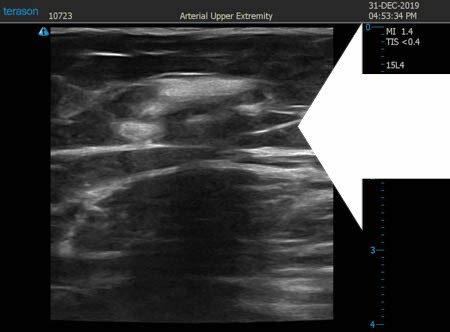

いつものように3Dタッチビュー(超音波)で

皮下脂肪層を評価してみましょう。

左太もも前面。